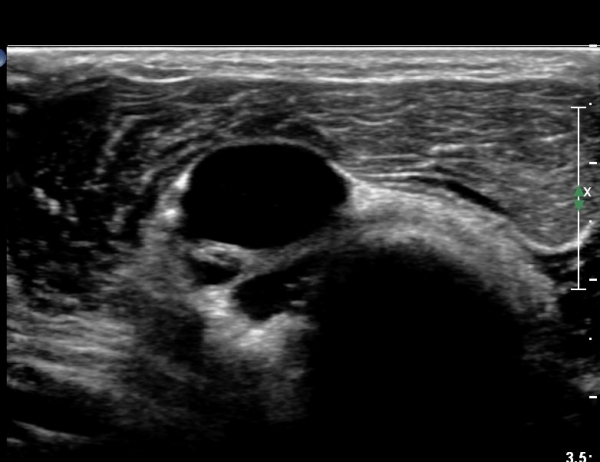

ŽÃËÀÚ¸¦ ¾à°£ ¸»´ÜÀ¸·Î À̵¿ÇÏ´Ï(¿ä°ñµÎ ºÎÀ§) Å« ³¶Á¾ÀÌ º¸ÀÌ°í ³¶Á¾ÀÇ ¿ÜÃø¿¡ Èİñ°£½Å°æÀÇ ¾Ð¹ÚÀÌ °üÂûµÈ´Ù(»çÁø 2). ³¶Á¾Àº ¿ä°ñµÎ¿¡¼­ ¿ä°ñºÎÀ§±îÁö À§Ä¡ÇØ ÀÖ´Ù(»çÁø 3)